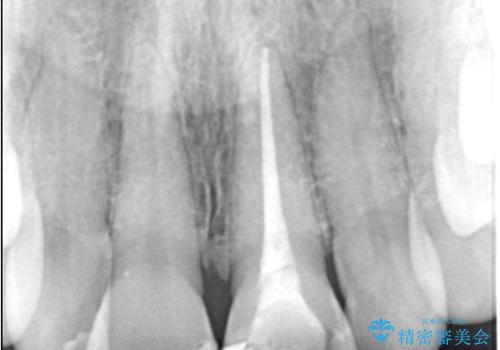

- 以前の根管治療後に生じた左上1番の前歯の変色を気にされて来院されました。患者様のご希望を伺い、オールセラミッククラウンによる審美修復を提案。既根管治療歯であるため、土台の状態や周囲の歯の色調を詳細に分析し、患者様の顔貌に調和した自然で美しい口元を実現するための治療計画を立てました。

治療では、変色した歯を形成した後、精密なシリコン印象材で型取りを行いました。この型取りから、患者様の歯の色や形、透明感を忠実に再現したオーダーメイドのオールセラミッククラウンを作製。金属を一切使わないため、アレルギーの心配がなく、歯ぐきの変色も防ぎます。技工士と連携し、天然歯と見分けがつかないほどの自然な仕上がりを追求。機能性と審美性を兼ね備えた、理想的な前歯を取り戻していただけました。